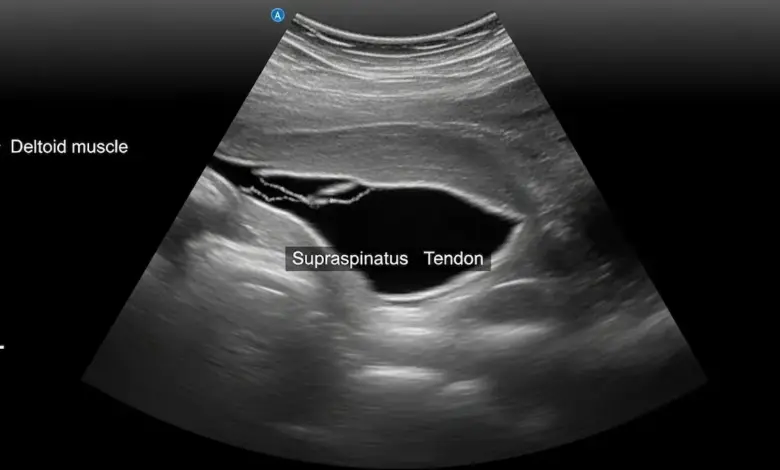

O diagnóstico começa com história clínica e exame físico, com testes que avaliam força, dor e estabilidade.

Exames de imagem entram para confirmar extensão e guiar o plano:

- Ultrassom é útil e acessível.

- Ressonância magnética detalha tendões, retração e qualidade muscular.

- Radiografia ajuda a avaliar esporões, calcificações e artrose associada.

Se você segue se perguntando por que lesionei o manguito rotador, a imagem não serve só para “dar nome”.

Ela ajuda a identificar se o caso é recente, se já havia degeneração, se existe impacto mecânico relevante e se há outras causas de dor, como bursite, tendinite do bíceps ou artrose acromioclavicular.